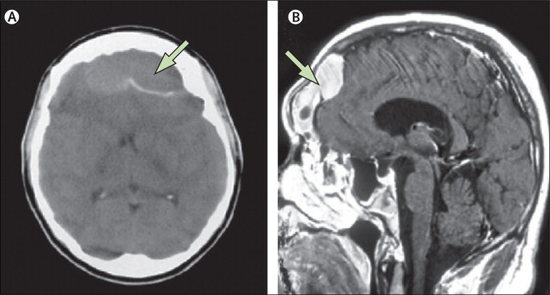

경막 외 농양의 MRI영상 경막 외 농양의 증상은 모호하고, 이마동염과 유사하고 있으므로, 앞머리 통증과 발열이 계속된다고 의심하고 볼 필요가 있습니다.농양이 커지면 뇌압이 상승하고, 국소 운동 장애, 감각 장애, 발작이 보입니다.CT, MRI에서 진단하고 소변 추천자가 정상적인 경우가 많습니다.